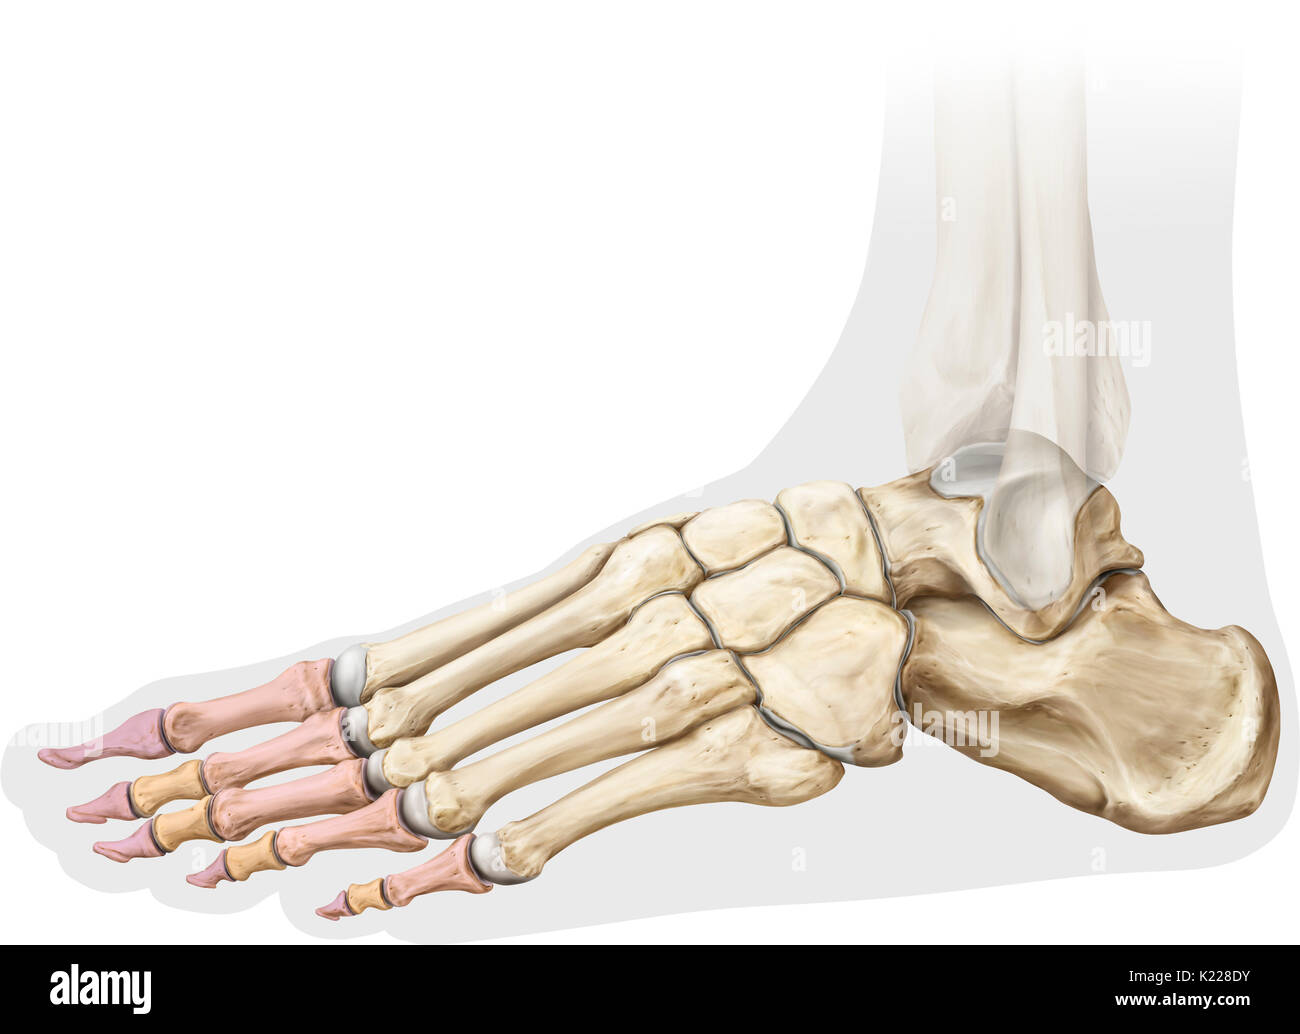

RMK228DY–Partie terminale du membre inférieur, reposant sur le sol au cours de posture droite ; le squelette du pied a 26 os.

RMK227XM–Partie terminale du membre inférieur, reposant sur le sol au cours de posture droite ; le squelette du pied a 26 os.